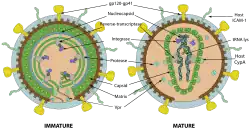

Im weiteren Verlauf folgt die Morphogenese, das heißt, über verschiedene Interaktionen finden die viralen Bestandteile wie Gag-, Pro-pol- und Env-Vorläuferproteine sowie die RNA zusammen und formen sich zu zunächst unreifen Virionen, die sich von der Plasmamembran abschnüren. Durch weitere Reifungsprozesse entsteht das reife Viruspartikel, bereit für die Infektion der nächsten Zelle. Zu den Reifungsprozessen gehört insbesondere die Spaltung der Vorläuferproteine – teils durch die virale Protease, teils durch zelluläre Enzyme – in ihre einzelnen Bestandteile, also von Gag in Matrix-, Kapsid- und Nukleokapsidprotein, Pol in Protease, Reverse Transkriptase mit RNase H und Integrase sowie Env in Oberflächen- und Transmembraneinheit. Die neugebildeten Tochtervirionen verlassen die Zelle durch Knospung. Beim Zusammenbau wird das HIV mit dem zellulären Protein Cyclophilin A bedeckt.[101] Dabei bindet je ein Cyclophilin A an zwei Hexamere des Kapsidproteins, wodurch es das Kapsid stabilisiert und maskiert vor intrazellulären Mechanismen der angeborenen Immunantwort in Makrophagen und dendritischen Zellen.[101]